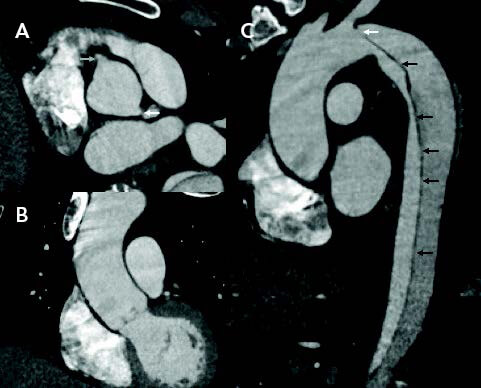

The combination of rapid patient movement through the CT scanner and the dual energy acquisition have allowed imaging of the aorta to be acquired between two heart beats, which then images the ascending aorta with little or no motion. The coronary cusps, ascending aorta, and transverse arch are free from artifact, so diagnosing a subtle type A dissection becomes much easier for the clinician and can be made with confidence (Figure 1A). If this imaging protocol is utilized, it negates the need for a confirmatory TEE in many cases. The lack of motion of the aorta during image acquisition improves the resolution and allows for accurate measurement of the aorta, as the wall is easy to identify (Figure 1B). In cases of acute and subacute dissection, where oversizing can lead to a retrograde dissection with stent graft deployment, utilizing this technique allows measuring and planning with much more confidence and accuracy than standard image acquisition.

Figure 1. CT images using an ultrahigh-pitch protocol demonstrating well-visualized coronary origins (arrows) with no aortic motion (A); motionless ascending aorta, aiding in excluding a dissection and improving measurement accuracy (B); and the entry tear (white arrow) and multiple tiny fenestrations along the entire length of the intimomedial flap (black arrows) (C).

This not only allows for motion reduction in the ascending aorta but also a much more sensitive and specific image where submillimeter fenestrations can be identified (Figure 1C), which may influence decisions regarding stent graft length.